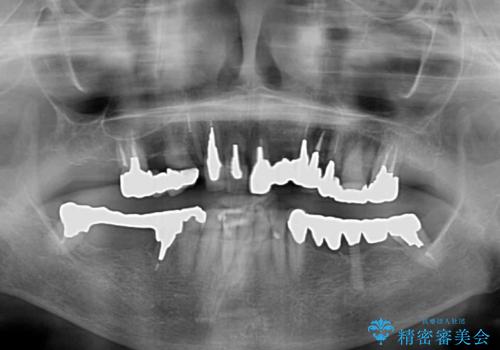

- 抜歯の必要な前歯や、以前治療した前歯のクラウンの外観を気にして来院された患者様です。

上顎犬歯や下顎大臼歯は、必要なところはインプラントを埋入することとしました。

クラウンが不適合であったり、根管治療の必要なほどの痛みのある歯であったり、見た目の気になる前歯などをオールセラミッククラウンに補綴治療を行うこととしました。